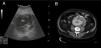

La ecografía en manos del internista permite responder preguntas clínicas concretas de forma rápida en el lugar de atención al paciente. Esta técnica «potencia» los sentidos del clínico y mejora su capacidad para resolver los problemas del enfermo. La ecografía clínica ha mostrado una buena precisión en el diagnóstico de diversas patologías cardíacas, abdominales y vasculares. También es útil para la evaluación de la patología tiroidea, osteoarticular y de partes blandas. Además, el uso de la ecografía para guiar procedimientos invasivos (accesos venosos, toracocentesis, paracentesis) reduce el riesgo de complicaciones. Presentamos 5casos para ilustrar la utilidad de esta técnica en la práctica clínica habitual del médico internista: a)miocardiopatía periparto; b)ateromatosis carotídea subclínica; c)aneurisma de aorta abdominal asintomático; d)tendinitis de los tendones largo del bíceps braquial y supraespinoso, y e)hematoma espontáneo en sóleo.

Ultrasonography in the hands of the internist can answer important clinical questions quickly at the point of patient care. This technique “enhance” the senses of the physicians and improves their ability to solve the problems of the patient. Point of care ultrasonography performed by clinicians has shown good accuracy in the diagnosis of diverse cardiac, abdominal and vascular pathologic conditions. It may also be useful for evaluation of thyroid, osteoarticular and soft tissue diseases. Furthermore, the use of ultrasound to guide invasive procedures (placement of venous catheters, thoracentesis, paracentesis) reduces the risk of complications. We present 5cases to illustrate the usefulness of this technique in clinical practice: (i)peripartum cardiomyopathy; (ii)subclinical carotid artery atherosclerosis; (iii)asymptomatic abdominal aortic aneurysm; (iv)tendinitis of long head of biceps brachii and supraspinatus, and (v)spontaneous soleus muscle haematoma.